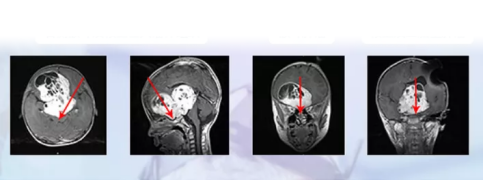

術(shù)前MR

視神經(jīng)膠質(zhì)瘤術(shù)前